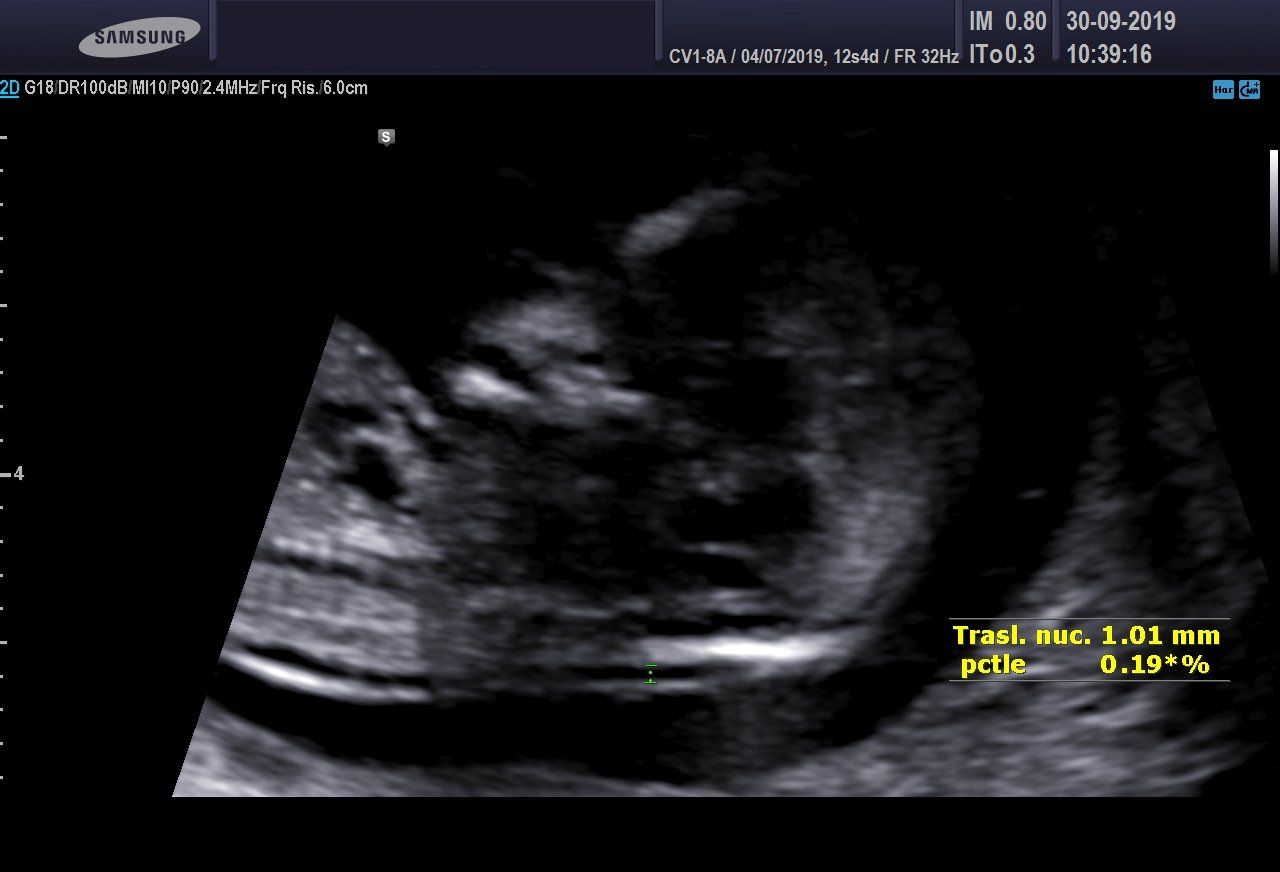

Screening del I Trimestre

È in atto il metodo più attendibile e non invasivo nel corso della gravidanza per valutare il rischio di avere un bimbo con un problema cromosomico, come per esempio la Sindrome di Down.